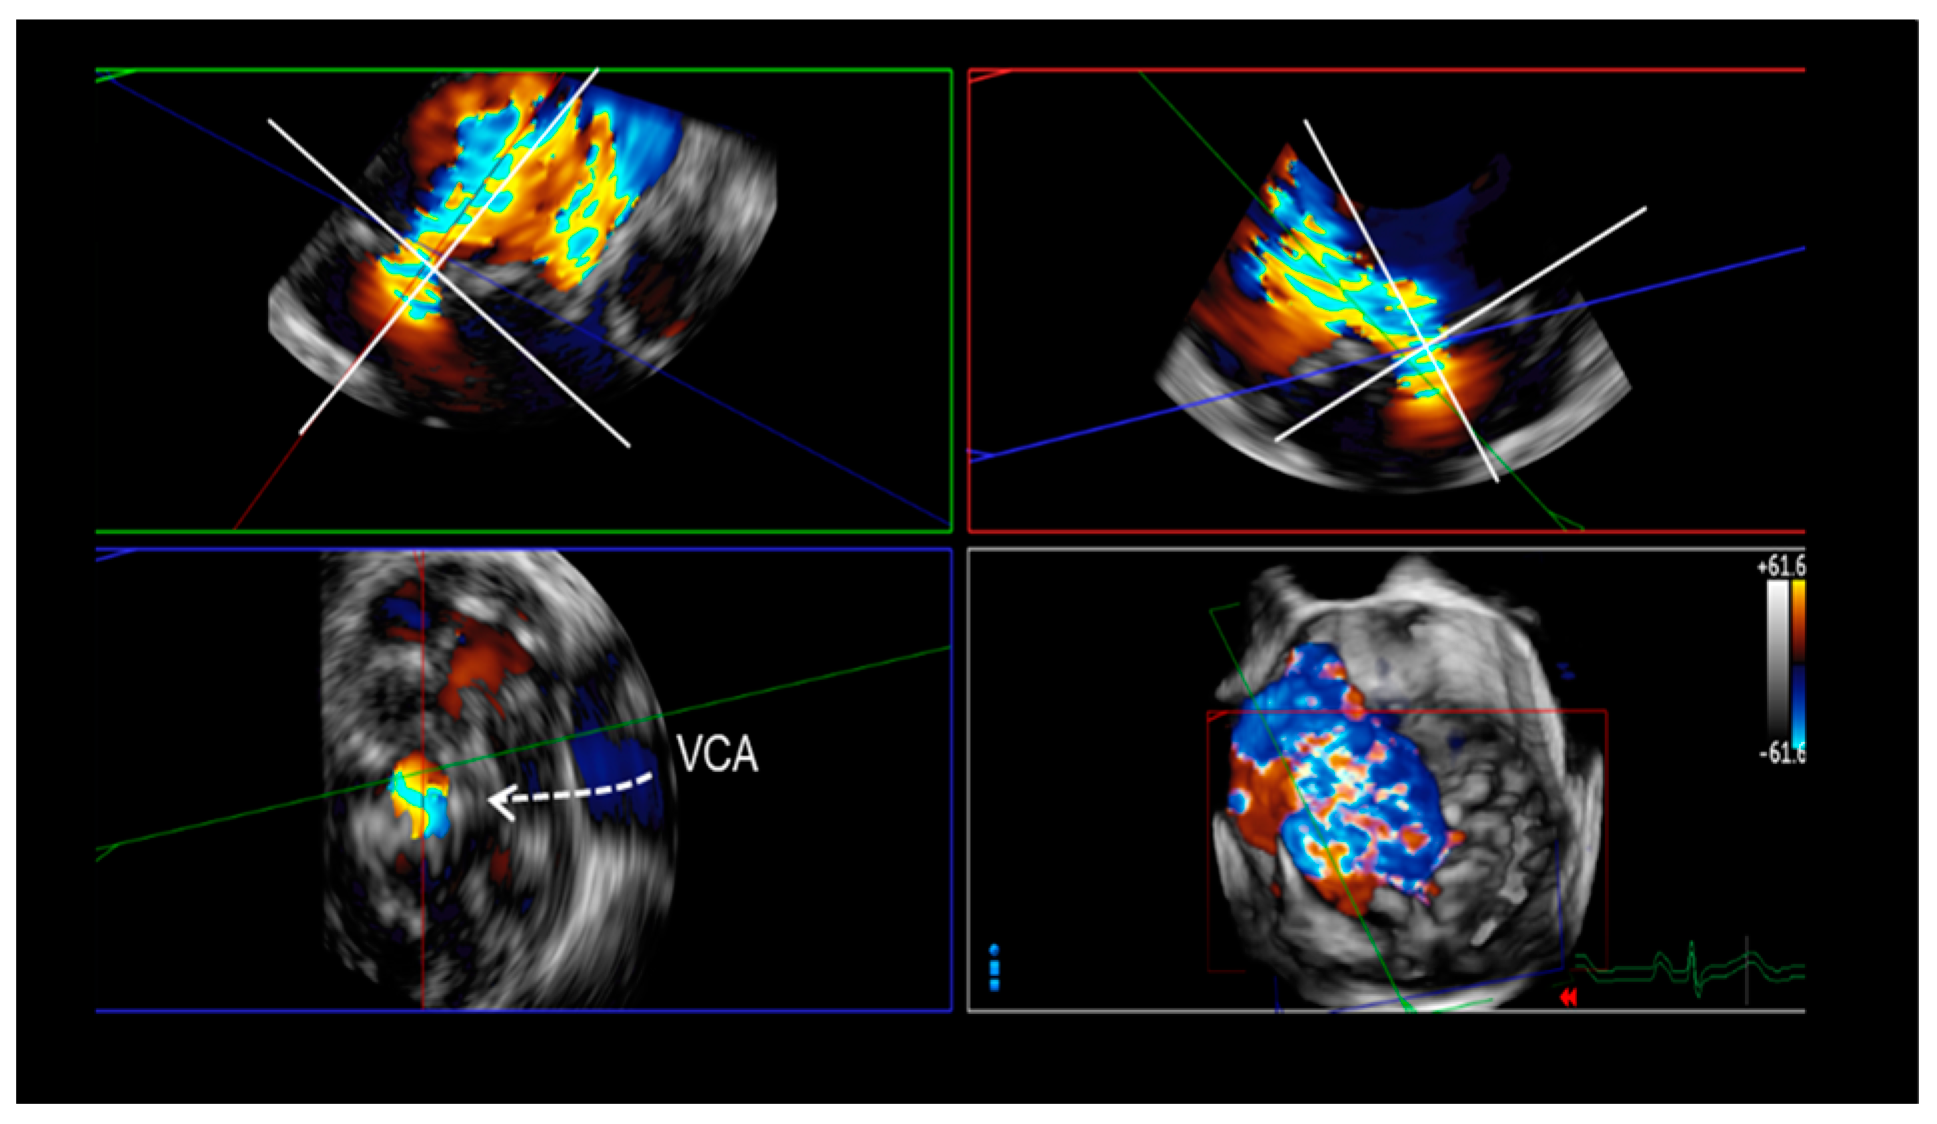

5. Assessment of Regurgitation Severity

Current Modalities

6. A New Tool